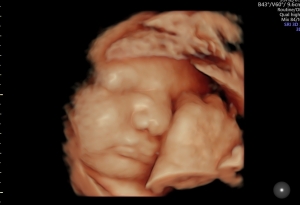

Sie können sich rund um die Uhr selbst den gewünschten Termin buchen. Besuchen Sie ggf. vorab den „Schwangerschaftskalender“ und dann die unsere Terminvergabe auf